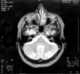

Hypereosinophilic syndrome is a disease characterized by a persistently elevated eosinophil count (≥ 1500 eosinophils/mm³) in the blood for at least six months without any recognizable cause, with involvement of either the heart, nervous system, or bone marrow.HES is a diagnosis of exclusion, after clonal eosinophilia (such as FIP1L1-PDGFRA-fusion induced hypereosinophelia and leukemia) and reactive eosinophilia (in response to infection, autoimmune disease, atopy, hypoadrenalism, tropical eosinophilia, or cancer) have been ruled out.There are some associations with chronic eosinophilic leukemia as it shows similar characteristics and genetic defects. If left untreated, HES is progressive and fatal. [Source: Wikipedia ]